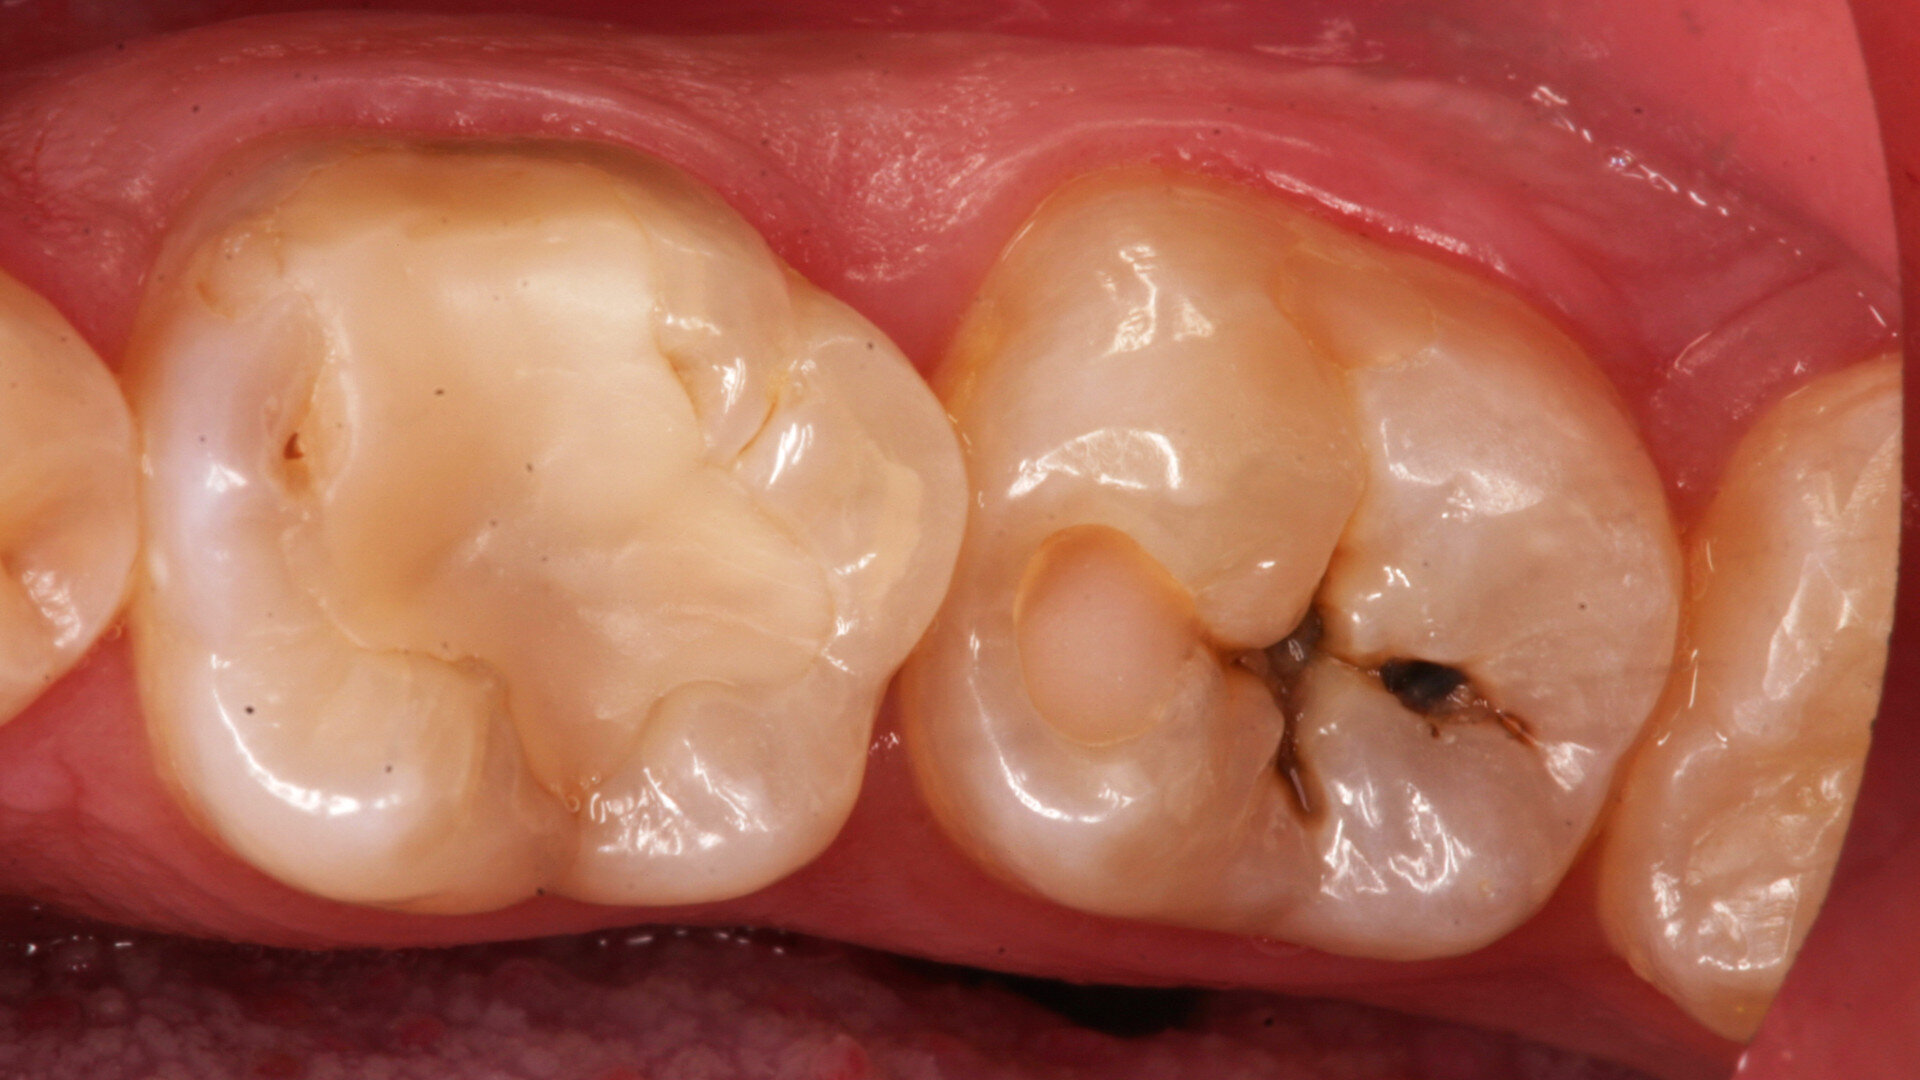

Le cas n° 2 montre une deuxième molaire inférieure présentant une carie profonde. Aucune douleur n’a été signalée par le patient, et la vitalité de la dent a été confirmée avant l’injection de l’anesthésie.

Après la mise en place de la digue pour garantir un champ propre et empêcher toute contamination salivaire et bactérienne pendant l’excavation de la carie. Une fraise ronde en carbure de tungstène sur contre-angle bague bleue (1:1) a été utilisée à vitesse et pression faibles pour éviter de surchauffer les tissus pulpaires. La figure 11 montre la cavité préparée après l’élimination des caries ainsi que la pulpe visible par transparence.